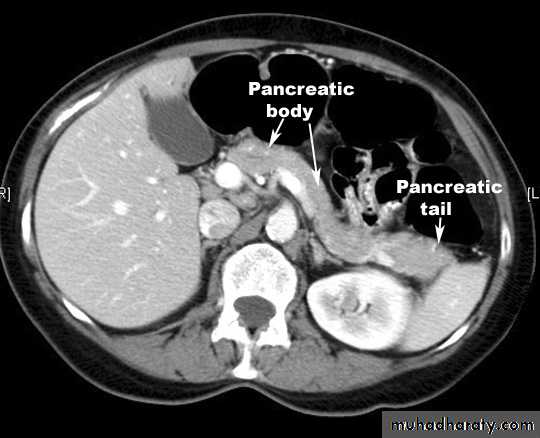

Made up of head, neck body and tailRetroperitoneal

Head lies in the ‘C’ of the duodenum

also overlies IVC, L2 vertebra, medial aorta and superior mesenteric vessels

Behind the neck splenic veins joins superior mesenteric vein to form portal vein

Pancreatic duct closely related to common bile duct